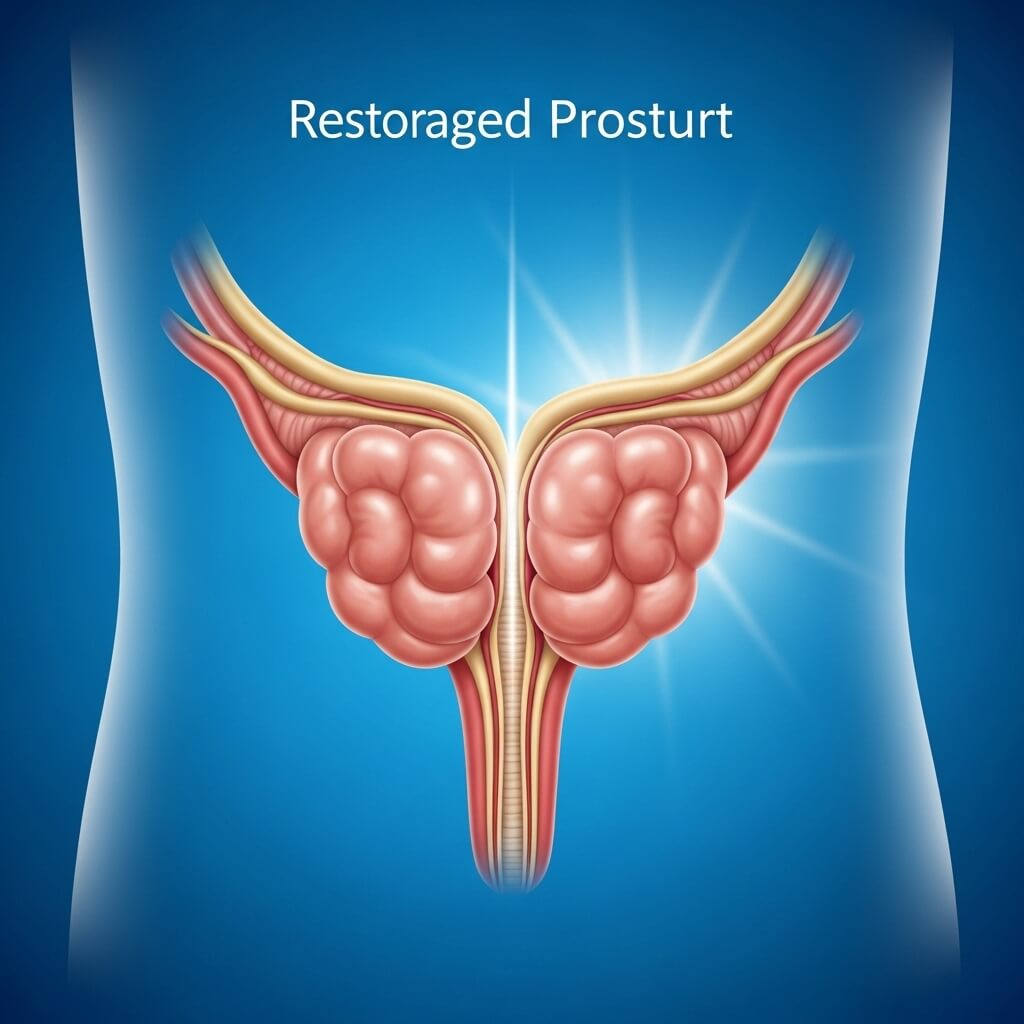

Professor discovers why SpaceX astronauts NEVER suffer from prostate problems and reveals 15-second zero-gravity trick

What you're about to see is the exact internal transformation thousands of men

experienced after following the 15-second japanese ritual now backed by NASA-

level science.

What stage are YOU in right now?

Watch how this simple 15-second ritual is restoring freedom to men over 40 - whithout drugs, doctors, or diapers.

NASA COVERED UP AN $84 BILLION DISCOVERY TO PROTECT BIG PHARMA'S PROFITS

They uncovered a prostate breakthrough in 1973...

But hid it from the public for over 50 years. Why? Because healthy men don't make money.

CLASSIFIED DOCUMENT #4-7829-B:

"The zero gravity environment significantly reduces pressure on the prostate gland, leading to a measurable drop in inflamatory response. Subjects experienced dramatic improvements in

urinary comfort and frequency within 72 hours of orbital exposure."

- NASA Medical Research division, 1973 (CLASSIFIED UNTIL 2040)

This leaked NASA file was never meant to be seen...